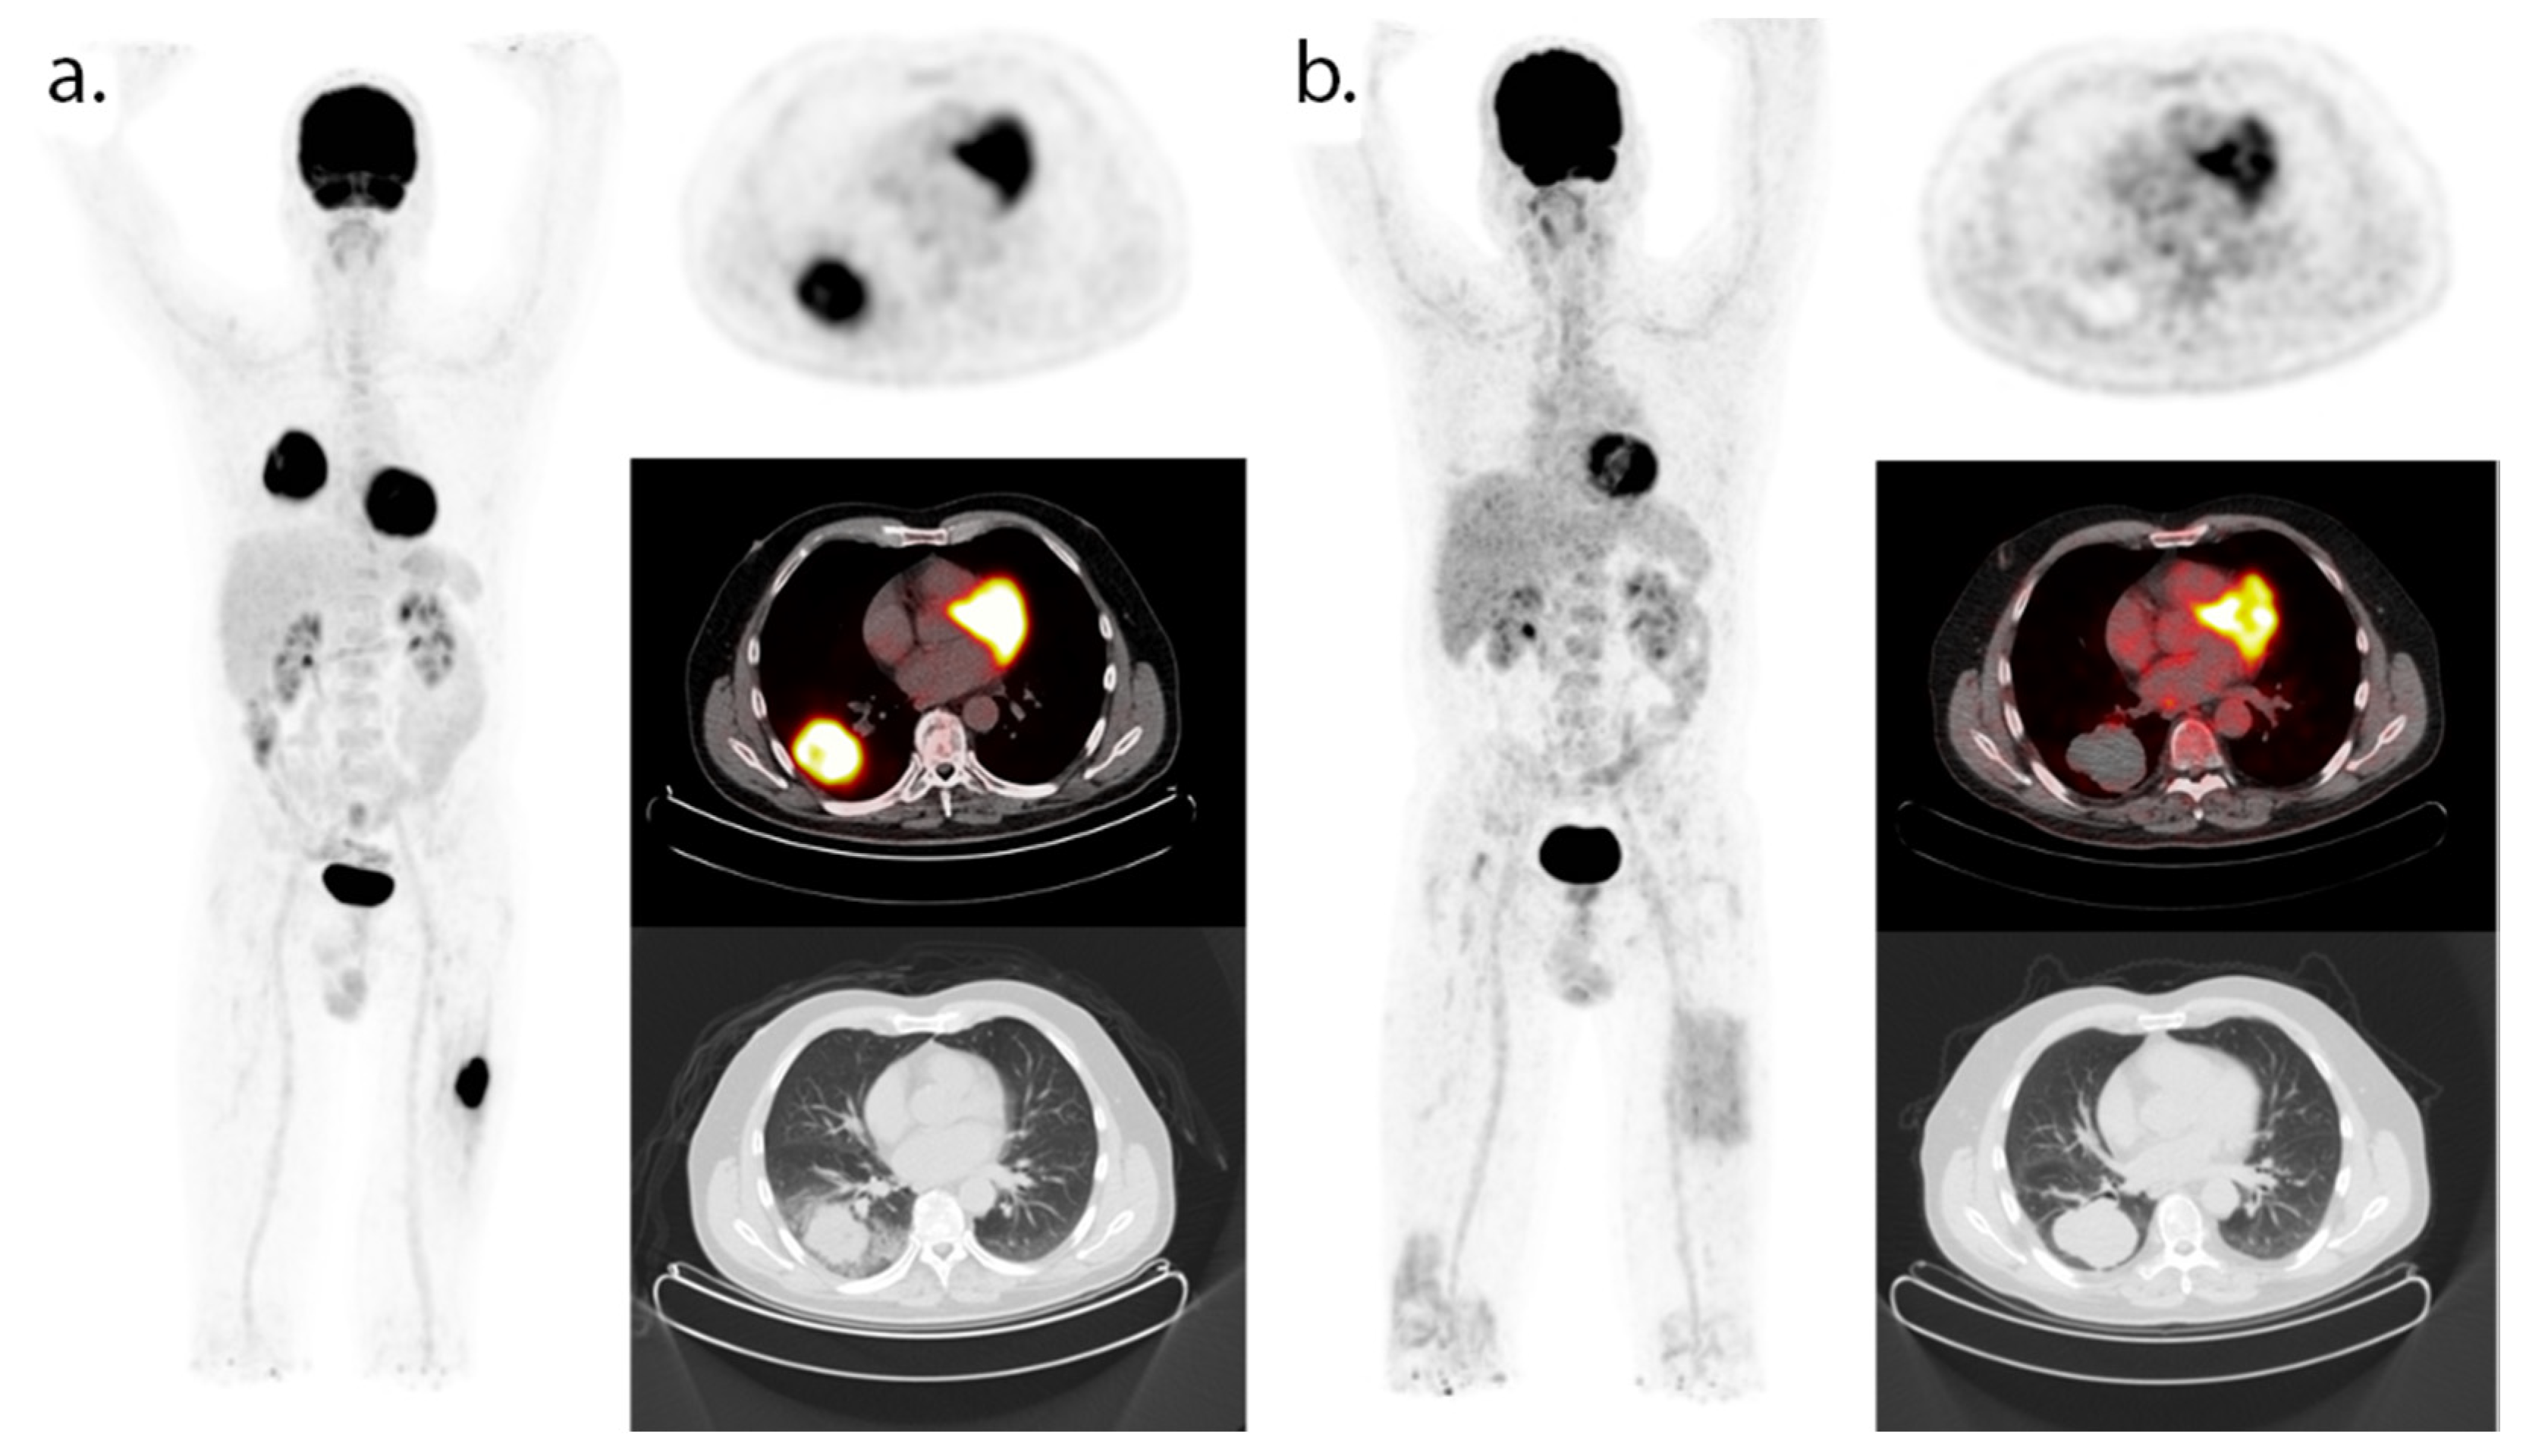

- Cho, S.Y.; Lipson, E.J.; Im, H.J.; Rowe, S.P.; Gonzalez, E.M.; Blackford, A.; Chirindel, A.; Pardoll, D.M.; Topalian, S.L.; Wahl, R.L. Prediction of response to immune checkpoint inhibitor therapy using early-time-point 18F-FDG PET/CT imaging in patients with advanced melanoma. J. Nucl. Med. 2017, 58, 1421–1428. [Google Scholar] [CrossRef] [PubMed] [Green Version]

- Sachpekidis, C.; Larribere, L.; Pan, L.; Haberkorn, U.; Dimitrakopoulou-Strauss, A.; Hassel, J.C. Predictive value of early 18F-FDG PET/CT studies for treatment response evaluation to ipilimumab in metastatic melanoma: Preliminary results of an ongoing study. Eur. J. Nucl. Med. Mol. Imaging 2014, 42, 386–396. [Google Scholar] [CrossRef]

- Seith, F.; Forschner, A.; Schmidt, H.; Pfannenberg, C.; Gückel, B.; Nikolaou, K.; La Fougère, C.; Garbe, C.; Schwenzer, N. 18F-FDG-PET detects complete response to PD1-therapy in melanoma patients two weeks after therapy start. Eur. J. Nucl. Med. Mol. Imaging 2018, 45, 95–101. [Google Scholar] [CrossRef] [PubMed]